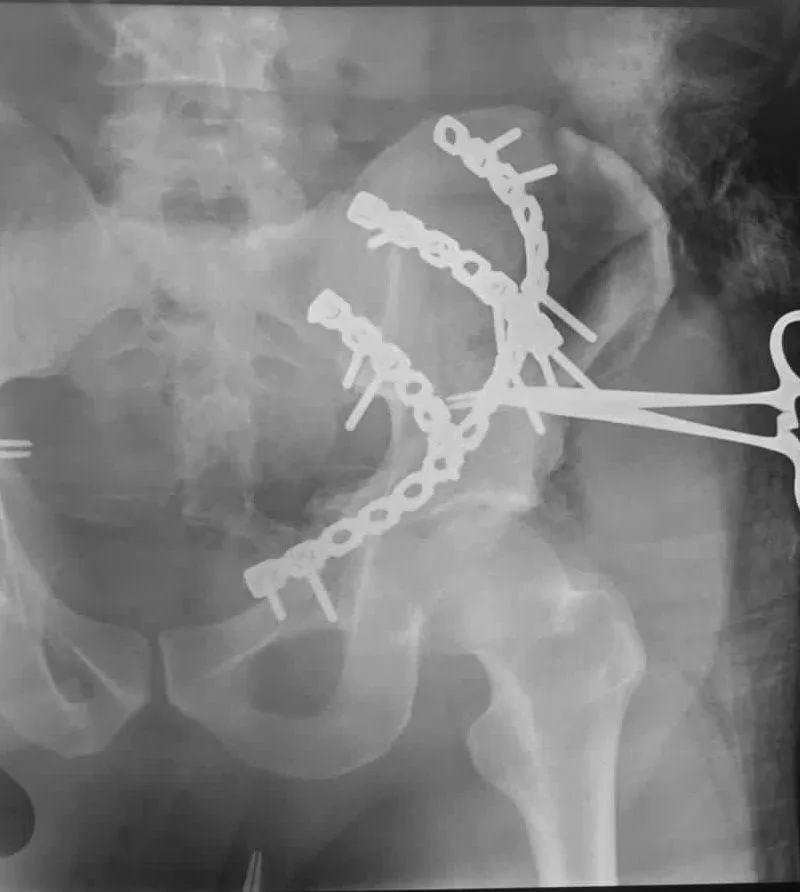

Fractura Antigua

Fractura antigua de cadera tratada con prótesis de doble movilidad

Fractura de cadera de larga evolución. Se realizó procedimiento quirúrgico con colocación de prótesis de doble movilidad.